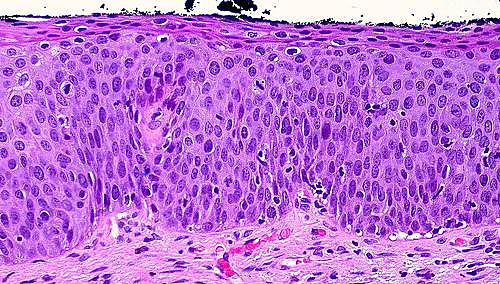

Entre las semanas 8 y 11, la proliferación de la capa basal forma una capa de células madre profundas al peridermo.

Hacia la semana 14, las células del estrato germinativo han formado una capa intermedia que se diferencia y contribuye a la formación de la epidermis queratinizada madura.